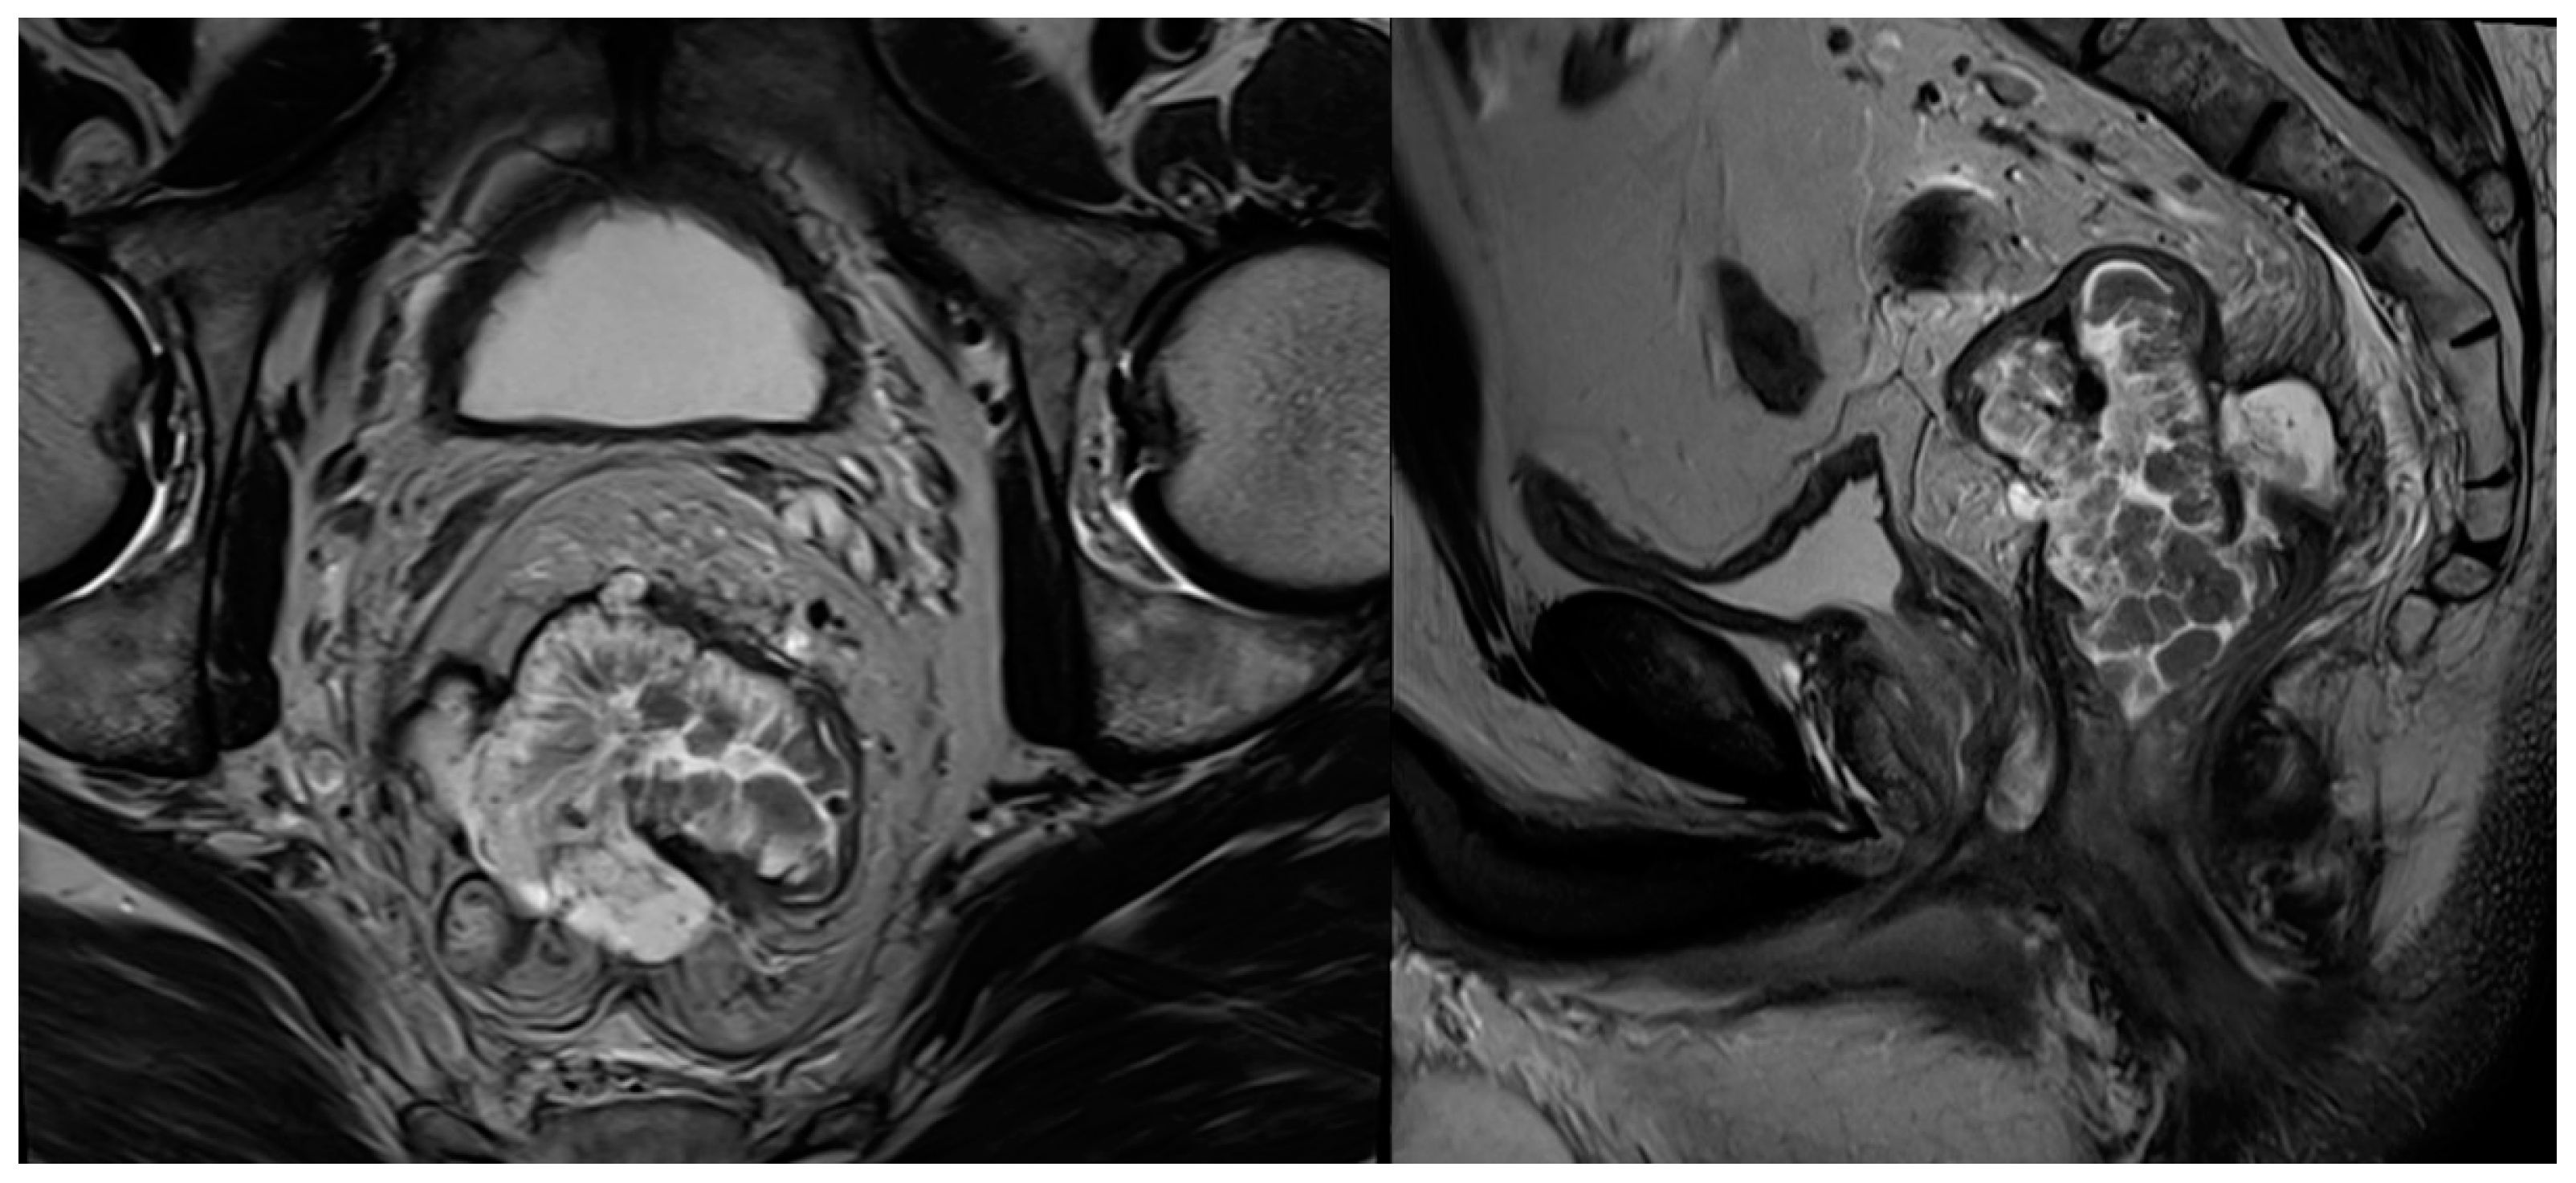

2.6. Mucinous Tumours

| Mucinous tumours | Mucin component is readily identified as high signal intensity on T2WI |